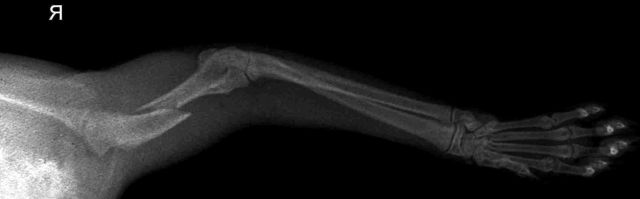

image

Диагностика в ветклинике

Если питомец получил травму, важно обратиться в ветеринарную клинику. Ветеринар осмотрит животное и проведет необходимые диагностические исследования, чтобы определить степень повреждения и назначить лечение.

К методам диагностики относятся общий и биохимический анализы крови, рентген в двух проекциях и ЭХО сердца. В некоторых случаях может потребоваться УЗИ брюшной полости.

Для диагностики проводят ряд исследований, позволяющих визуализировать место повреждения и разработать тактику лечения:

• общий клинический осмотр и сбор анамнеза;

• пальпация;

• рентгенологическое исследование.